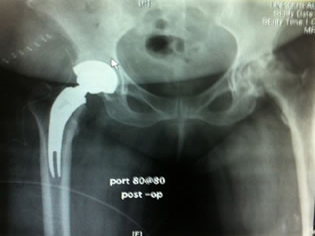

|

| X-ray confirmed our impression that we could go up in size of the stem and neck length. The offset appeared to be good with a neutral modular neck and 0 head with a 36 mm poly insert. |

Skin to Skin less than 60 minutes / with intraoperative x-rays, a new device in a challenging patient profile with a new O.R. team. This only happens because of the preoperative training of the surgeon. |